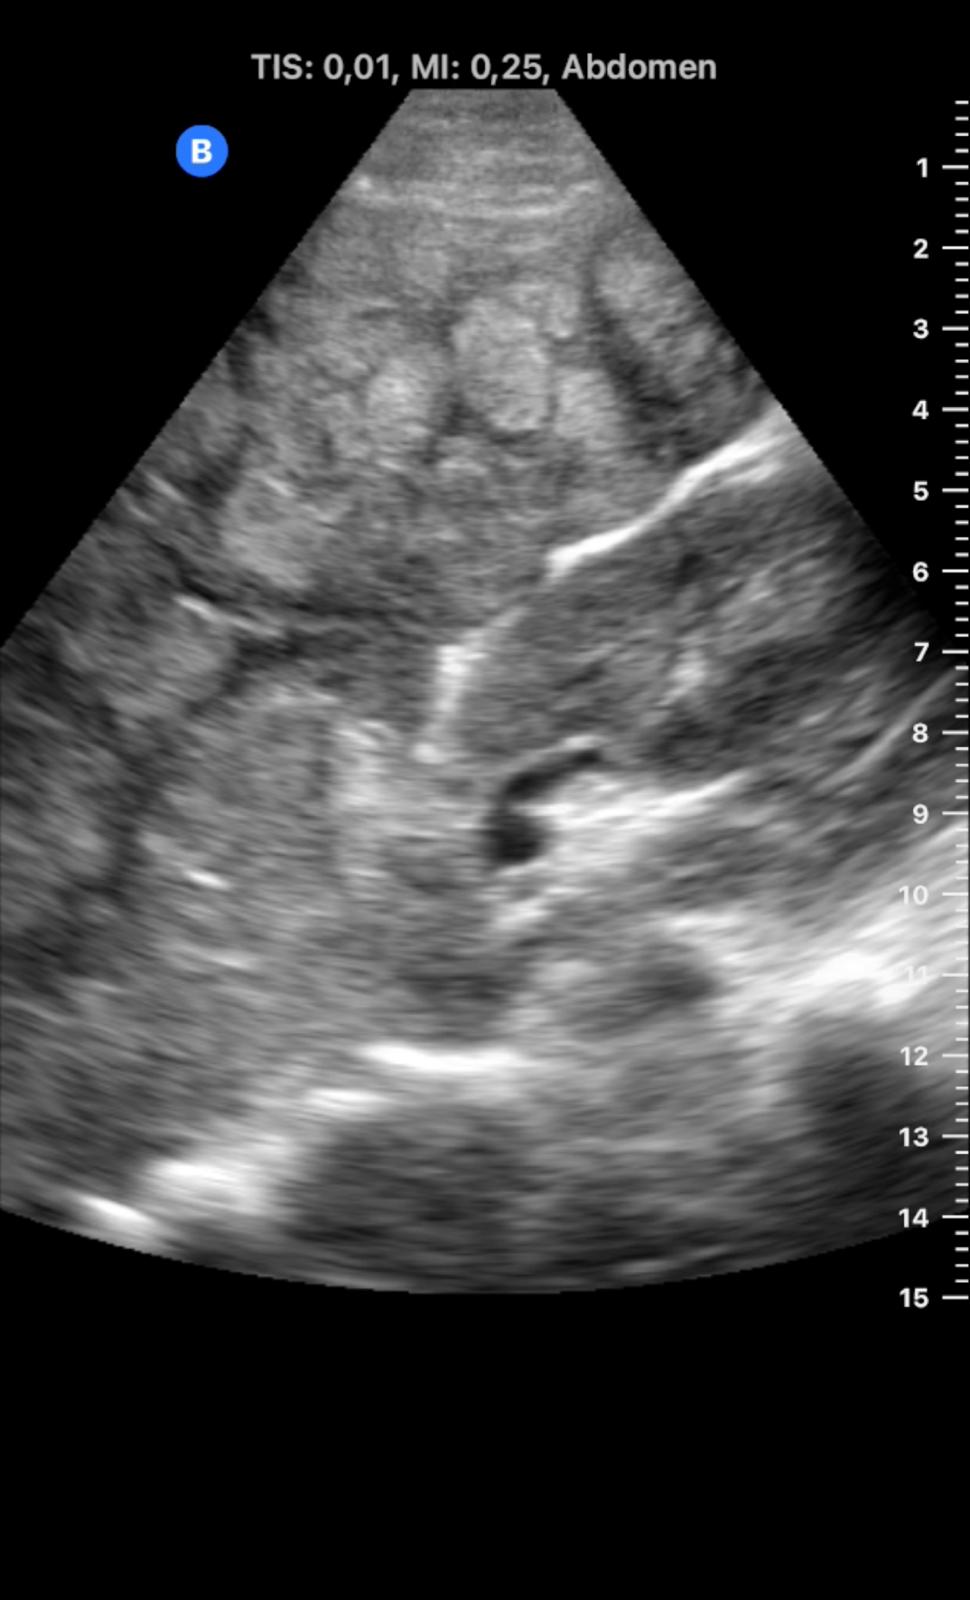

Descripción de los hallazgos ecográficos y las imágenes más relevantes para la resolución del caso

En ecografía en Centro de Salud: La práctica totalidad del parénquima hepático se encuentra sustituida por múltiples lesiones sólidas nodulares hiperecoicas, de predominio en el lóbulo hepático derecho, donde presentan tendencia a la confluencia y conforman una masa que alcanza los 13 cm de diámetro máximo. La vena porta es permeable y ectásica, con esplenomegalia. Ambos son signos de hipertensión portal.

Ante estos hallazgos se deriva al paciente a Urgencias.